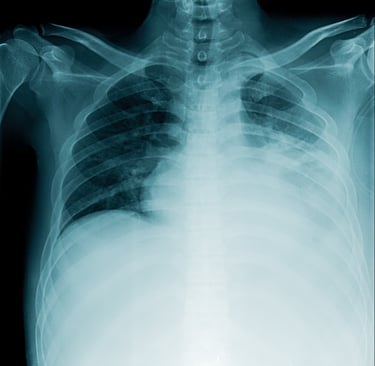

Tuberculosis

Tuberculosis (TB) remains one of the world’s deadliest infectious diseases, killing nearly two-thirds of untreated patients within three years. While curable with proper treatment, delays or incomplete care allow the disease to progress, leading to severe illness, drug resistance, and death.

TB often lurks silently: 1 in 4 people worldwide carries latent TB, with a 5–10% lifetime risk of it becoming active. For those with weakened immune systems—such as people living with HIV—the risk skyrockets to 10% per year. HIV co-infection makes TB harder to treat and deadlier, with higher failure rates and mortality.